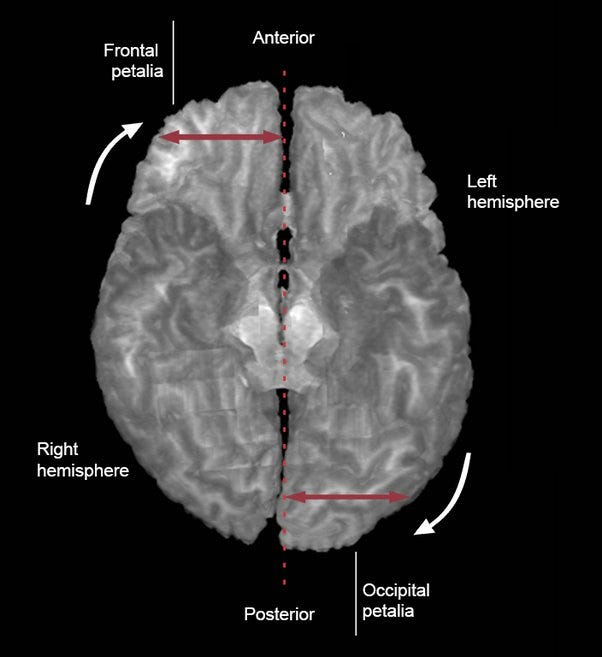

A surprising aspect of our brain is how asymmetrical and lateralized it is. Along with having two hands, two eyes, two legs, two nostrils, and two lungs, we have two distinct sides of our brain: the right hemisphere and the left hemisphere. These two sides are connected by a small, but dense thread of nerves called the corpus callosum.

As animals get larger and more complex, the two sides of the brain also become more asymmetrical. In humans, the left hemisphere alone is responsible for speech (this is true of many other animals too—the left hemisphere of songbirds actually expands during mating season, and then shrinks again once the mating season is over and complex calls are less necessary) and it is dominant in language comprehension.

The hemispheres differ in size, weight, shape, sulcal-gyral pattern (the convolutions on the cortical surface), neuronal number, cytoarchitecture (the structure at the cellular level), neuronal cell size, dendritic tree features, grey to white matter ratio, response to neuroendocrine hormones and degree of reliance on different neurotransmitters.”